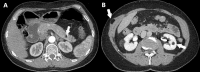

Results: The prevalence of angiofibromas was significantly higher in F-MEN1 than in S-MEN1 in both the whole (p < 0.001) and index case (p = 0.003) cohorts. The prevalence of lipomas was also significantly higher in F-MEN1 than in S-MEN1 (p = 0.009) and in MEN1 mutation-positive than in MEN1 mutation-negative (p = 0.01) index cases. In the whole cohort, the prevalence of lipomas was significantly higher in MEN1 mutation-positive compared to MEN1 mutation-negative patients (OR = 2.7, p = 0.02) and in F-MEN1 than in S-MEN1 (p = 0.03), only after adjustment for age. No significant differences were observed for the other non-endocrine manifestations between the two cohorts. Hibernoma and collagenoma were each present in one patient (0.5%) and meningioma and neuroblastoma in 2.7% and 0.5%, respectively. Gastric leiomyoma was present in 1.1% of the patients and uterine leiomyoma in 14% of women. Thyroid cancer, breast cancer, lung cancer, basal cell carcinoma, melanoma, and colorectal cancer were present in 4.9%, 2.7%, 1.6%, 1.6%, 2.2%, and 0.5% of the whole series, respectively.